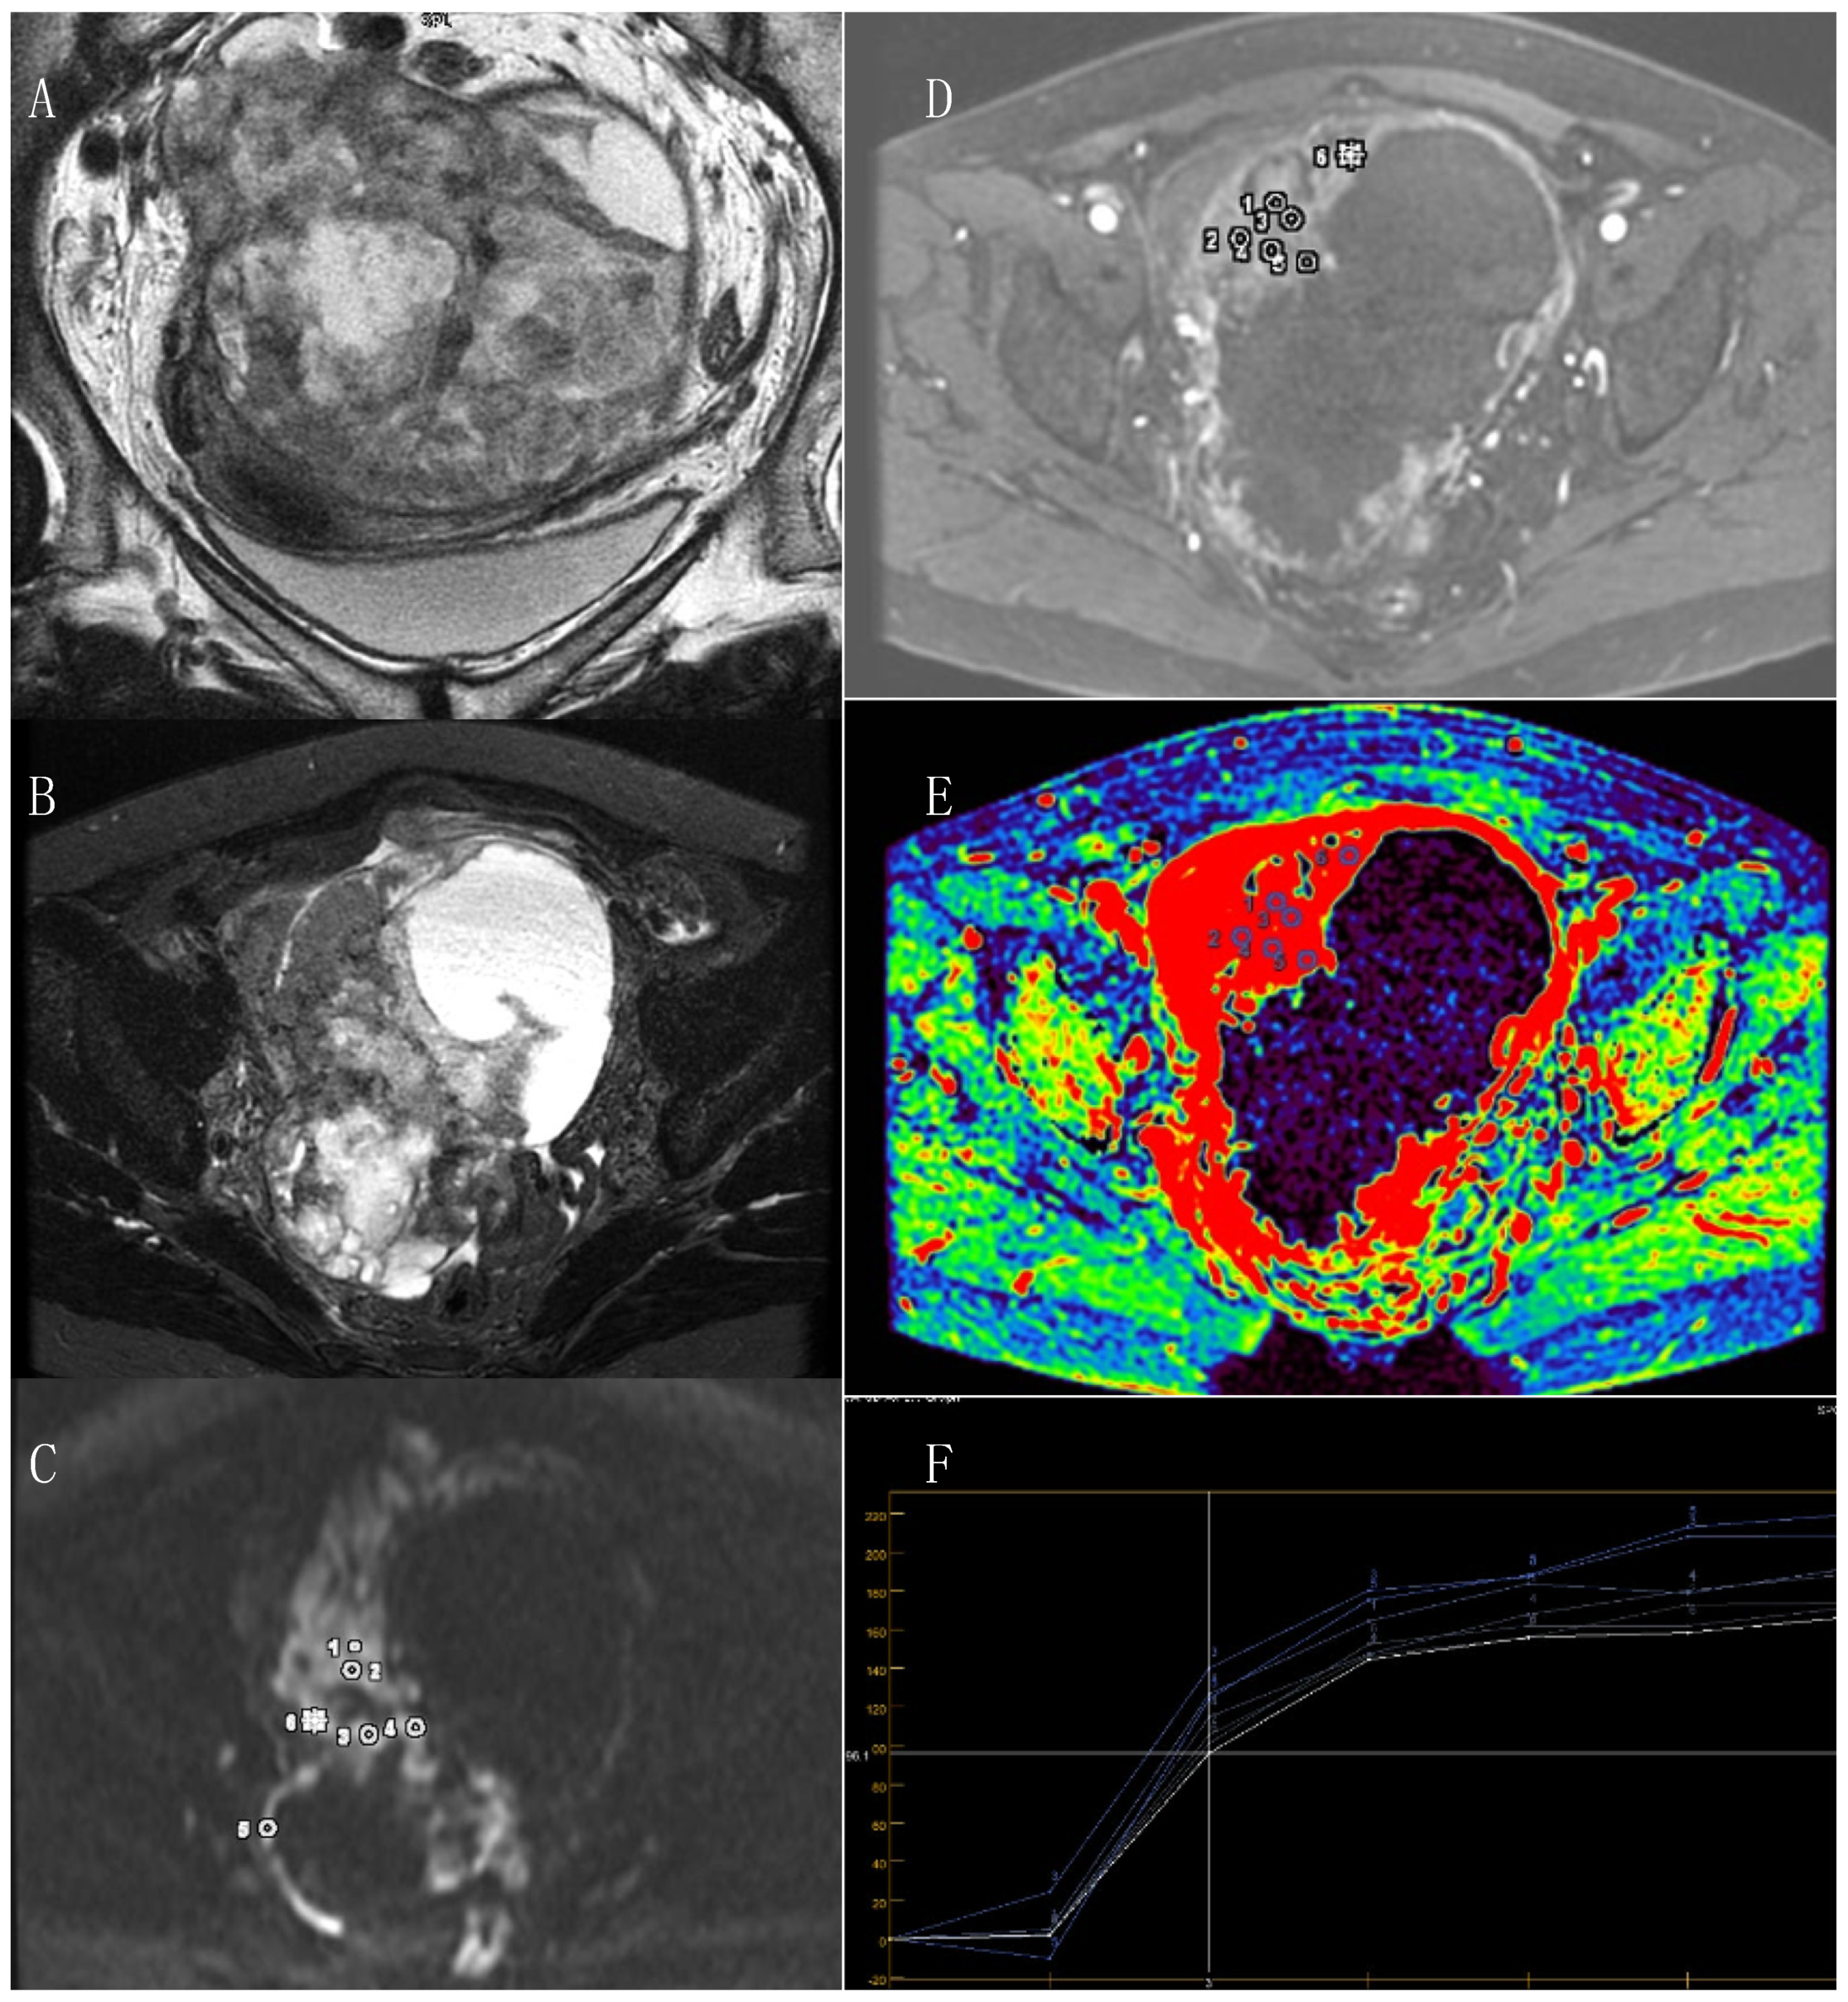

3.1. Primary Tumor

3.2. MRI DWI and DCE Parameters and Immunohistochemistry

3.3. Relapse of the Disease